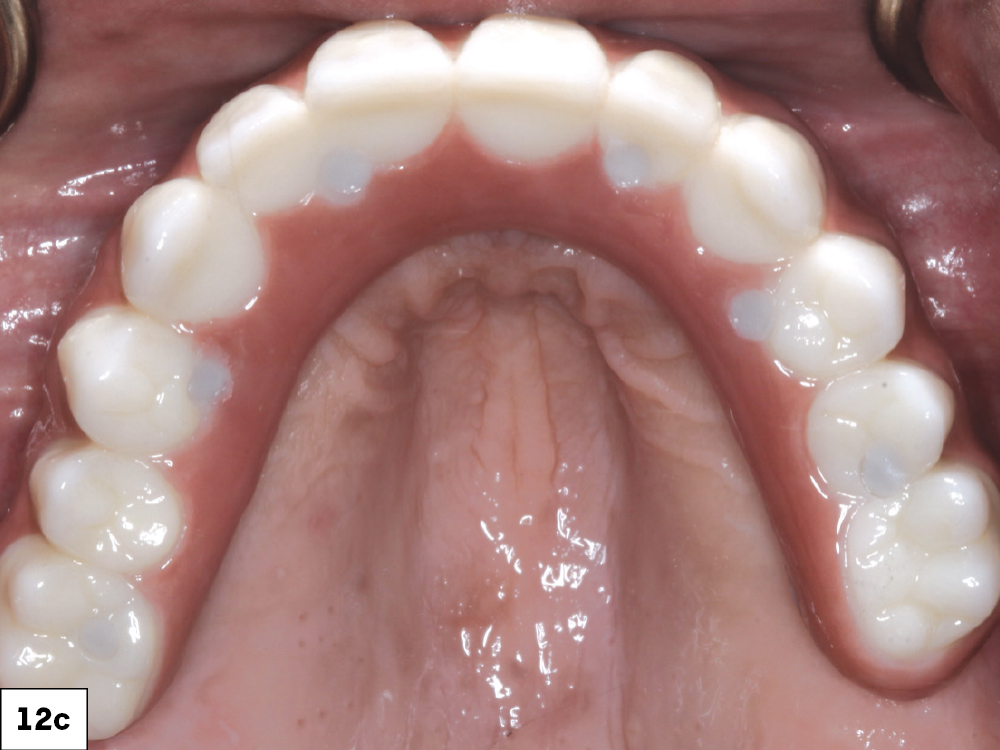

Once the first denture setups were tried in over the multi-unit abutments and approved, a polymethyl methacrylate (PMMA) provisional was milled. I then inserted this prosthesis and verified esthetics and function.

Figures 12a–12c: Once the first denture setups were tried in over the multi-unit abutments and approved, a polymethyl methacrylate (PMMA) provisional was milled. I then inserted this prosthesis and verified esthetics and function.